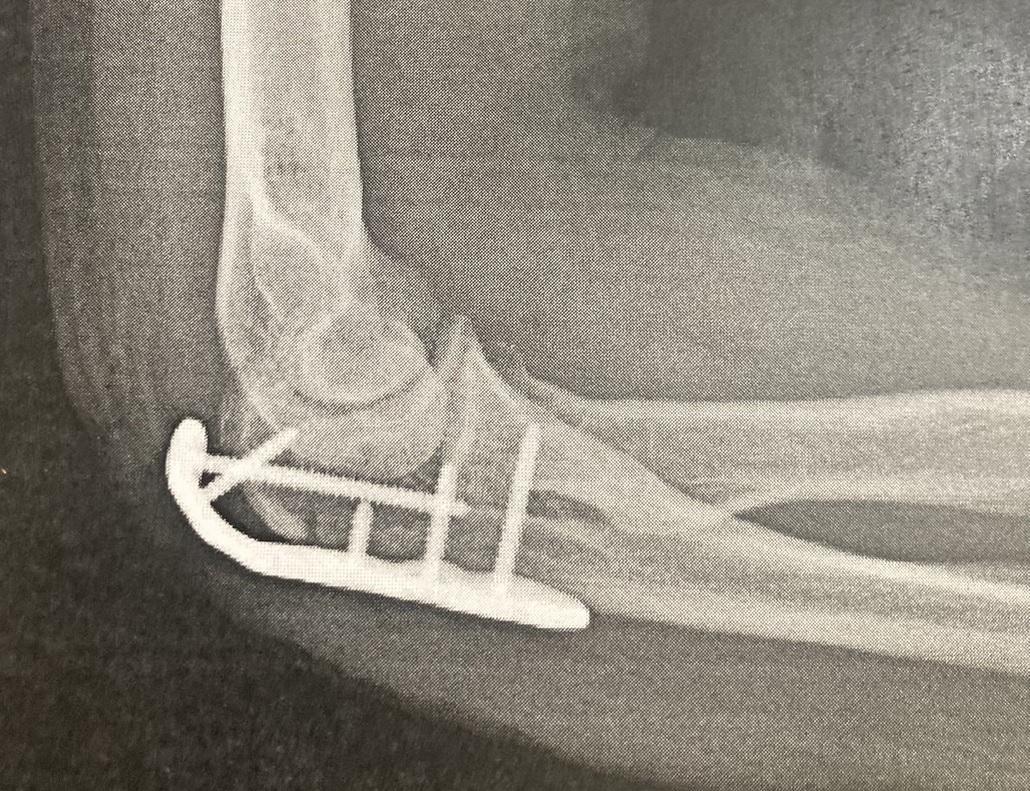

• レントゲンで見ると手首の中にガッツリ埋め込まれたネジとプレート

レントゲンで見ると手首の中にガッツリ埋め込まれたネジとプレート

• 肘にもしっかり埋め込まれています。

肘にもしっかり埋め込まれています。